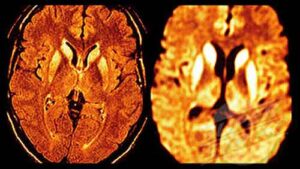

Una improvvisa perdita di udito da entrambi i lati puo’ essere un sintomo del morbo di Creutzfeldt-Jakob, una patologia della stessa famiglia della ‘mucca pazza’.Creutzfeldt-Jakob Lo afferma uno studio dell’ospedale Henry Ford di New York che verra’ presentato al prossimo congresso della American Academy of Neurology. La conclusione e’ dovuta al caso di un uomo di 67 anni curato dall’ospedale che ha perso l’udito a entrambe le orecchie progressivamente per due mesi, e a cui solo dopo e’ stata diagnosticata la malattia. Secondo i neurologi dell’ospedale e’ solo la quarta volta che e’ possibile documentare questo sintomo associato al morbo, ma le evidenze sono tali che i medici dovrebbero prendere in considerazione l’ipotesi quando riscontrano una perdita di udito di questo tipo: “La sordita’ – spiegano – e’ stata seguita dal declino cognitivo tipico della malattia, che ha portato a morte in un mese”.